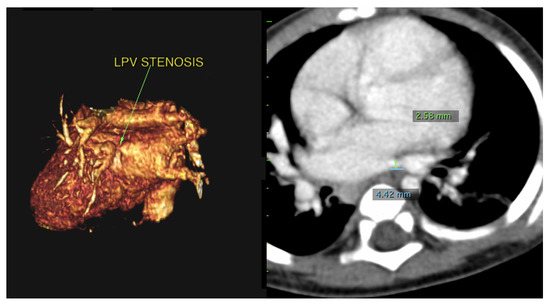

Using PVS as an initial search term, 57 cases from 24 different institutions were identified and included for analysis. Table 1 is a list of the institutions reporting cases of PVS and Figure 1 is a map of this. Figure 2 and Figure 3 are of a computed tomographic (CT) scans performed on described cases from Malaysia (Figure 2) showing repaired TAPVR with recurrent stenosis and Vietnam (Figure 3) showing idiopathic common left pulmonary vein stenosis.

Figure 3.

CT scans from the above described patient from Vietnam with left common pulmonary vein stenosis. The left image is a 3D reconstruction of a CT angiogram with the view of the left pulmonary vein connection to the left atrium. The arrow denotes the area of stenosis. The right image is a traditional CT angiogram with sternum anterior and spine posterior. The green marker is of the stenosis which narrows to 2.58 mm. The blue marker is of the length of the area of stenosis which is 4.42 mm.

“The patient was a 9-month-old who presented due to cough and shortness of breath. An echocardiogram revealed a small perimembranous ventricular septal defect (VSD) that was not hemodynamically significant and routine follow up was recommended. She continued to have respiratory difficulty at home and re-presented. A repeat echocardiogram re-demonstrated the VSD and showed left pulmonary vein stenosis. She was admitted for a CT which showed 2 left pulmonary veins to a common left pulmonary vein with stenosis at the common vein to left atrial connection. Right pulmonary veins were normal. She underwent VSD closure and sutureless anastomosis for left pulmonary veins 2 months later. The repair was delayed because of other urgent cases at the institution (Figure 3).”—Dinh Quang Le Thanh, MD, MS, Pediatric General and Cardiac Surgeon, Children’s Hospital 1, Ho Chi Minh City, Vietnam